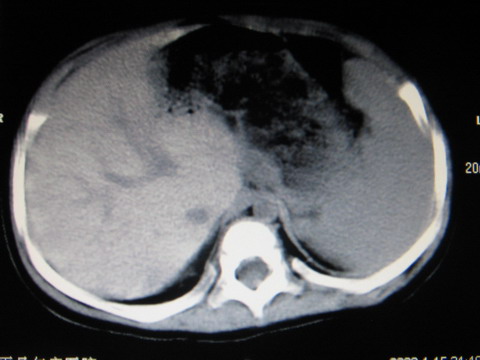

标题: PED0552:男1岁,双肾区CT [打印本页]

标题: PED0552:男1岁,双肾区CT

胎龄5个月时b超示左肾积水,现一岁后复查

左肾重度积水!

左肾重度积水!考虑肾盂输尿管交界处先天性狭窄或闭塞所导致